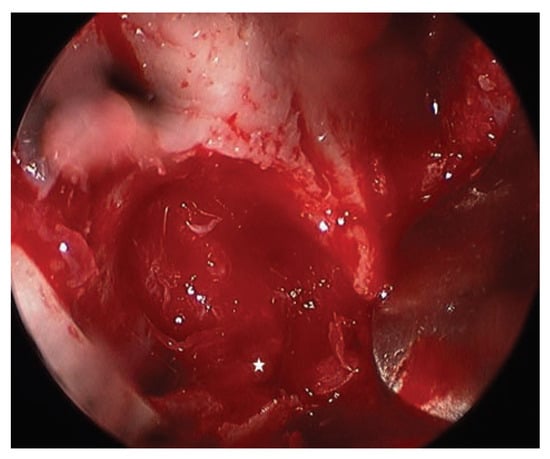

Report of a Case

![]() |